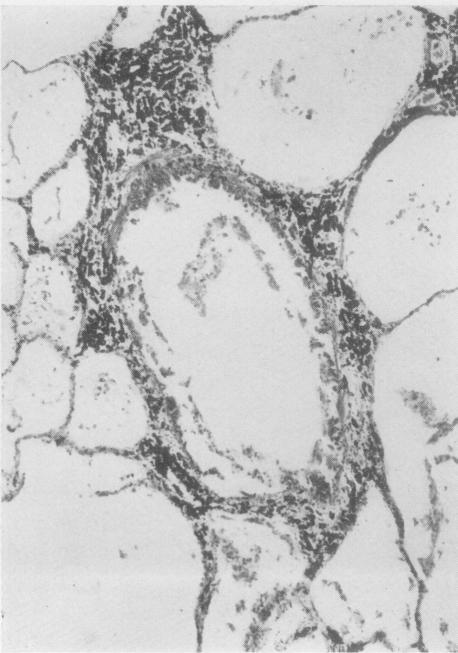

ESTERLY J R, HEARD B E

Thorax. 1965 Jul;20(4):309-16. doi: 10.1136/thx.20.4.309.